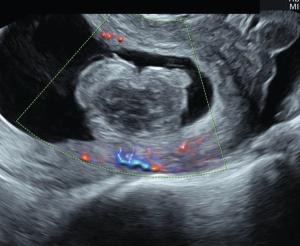

Pelvic sonography, especially transvaginal 3D imaging, is critical for identifying malpositioned and embedded IUDs.